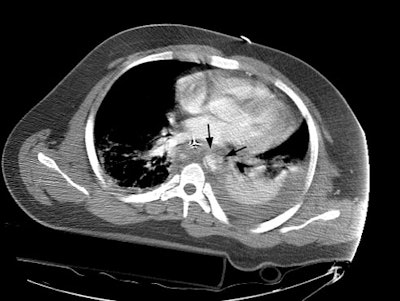

CT images more inferiorly revealed an intimal flap and marked irregularity to the contour of the aorta consistent with traumatic injury (black arrows). Slightly below this level there was a near complete lack of opacification of the vessel (lower image).